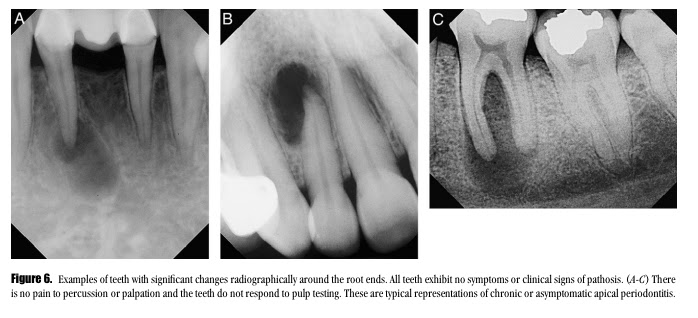

The diagnostic criteria of the different types of apical periodontitis.